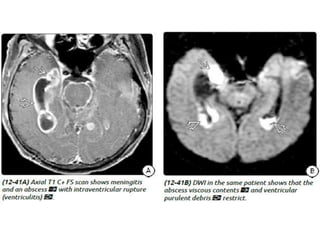

Ventriculitis

A collection of purulent material in the ventricle is more likely due to

intraventricular rupture of a brain abscess (IVRBA), a catastrophic

complication.

Imaging

CT

• Ventriculomegaly with a debris level in the dependent part of the

occipital horns.

• Periventricular hypodensity.

• The ventricular walls may enhance on CECT.

MRI

• Irregular ventricular debris that appears hyperintense to CSF on T1WI

and hypointense on

• T2WI with layering in the dependent occipital horns.

• A "halo" of periventricular hyperintensity is usually present on both

T2WI

• and FLAIR scans.

• DWI shows striking diffusion restriction of the layered debris.

• Ependymal enhancement is seen in only 60% of cases and varies from

minimal to moderate.